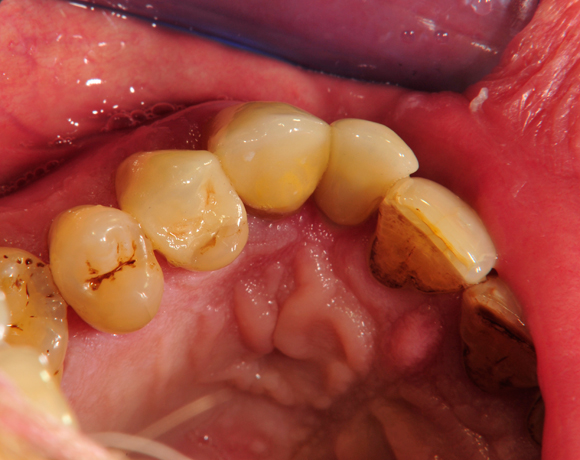

Bei diesem Patienten wurde der nichterhaltungswürdige Zahn 12 mit einem Zerameximplantat versorgt. Nach der Einheilphase wurden auch die Zähne 14 und 13 mit e.max Kronen versorgt